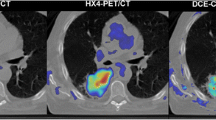

However, if the tumor is located in the thorax or abdomen, the patient’s breathing causes motion artifacts, resulting in misregistration between PET and CT images (Fig. 25.1) [5]. Because CT is used for attenuation correction of PET images, such misregistration affects image reconstruction. The patient’s breathing leads to marked displacement of most of the internal organs, from the apical region of the lungs down to the abdominal organs. Internal organ movement has a degrading effect on image quality and quantitative values in terms of spatial resolution and contrast [6]. Respiratory gating is a technique for improving the measurement of lesion uptake and tumor volume in PET/CT [7]. Motion management is becoming an important issue in both diagnostic and therapeutic applications. A series of studies in 18F-fluorodeoxyglucose PET/CT have shown that respiratory-gated (RG) 4D-PET/CT and breath-holding protocols allow compensation for image degradation and artifacts induced by respiratory movements [6]. In contrast, there has been no study in which RG FMISO-PET/CT was evaluated. We investigated the usefulness of respiratory gating in FMISO-PET/CT-based quantification of hypoxia.

In all the 14 patients, the tumor was visually identifiable from its higher signal intensities than the surrounding lung tissues (Figs. 25.3 and 25.4). Quantitatively, SUVmax, TMR, and TBR were all significantly higher on RG images (1.93 ± 1.11, 1.46 ± 0.78, and 1.42 ± 0.87, respectively) than on NG images (2.09 ± 1.11, 1.61 ± 0.78, and 1.53 ± 0.87, respectively) (Table 25.2, Fig. 25.5).